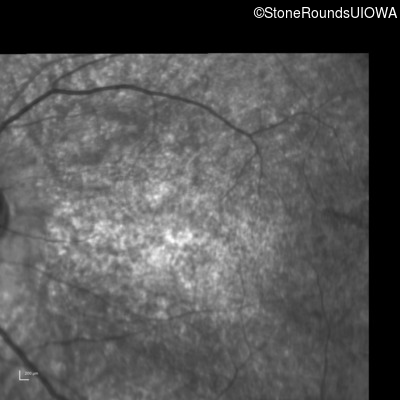

Infrared Fundus Photograph - Right - 10/200

Exemplar

Infrared Fundus Photograph - Left - 10/160 -1